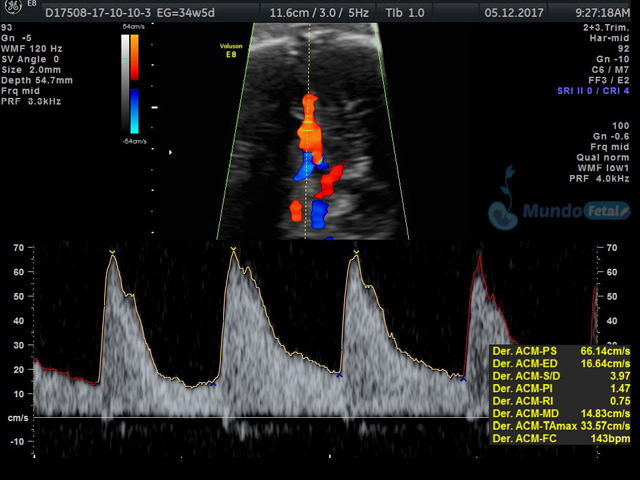

Se recomienda de 32-34 semanas, realizando valoración de crecimiento armónico (4 medidas específicas), valoración anatómica, líquido amniótico, flujos sanguíneos fetales y placentarios perfilando el bienestar fetal hacia el final de embarazo.